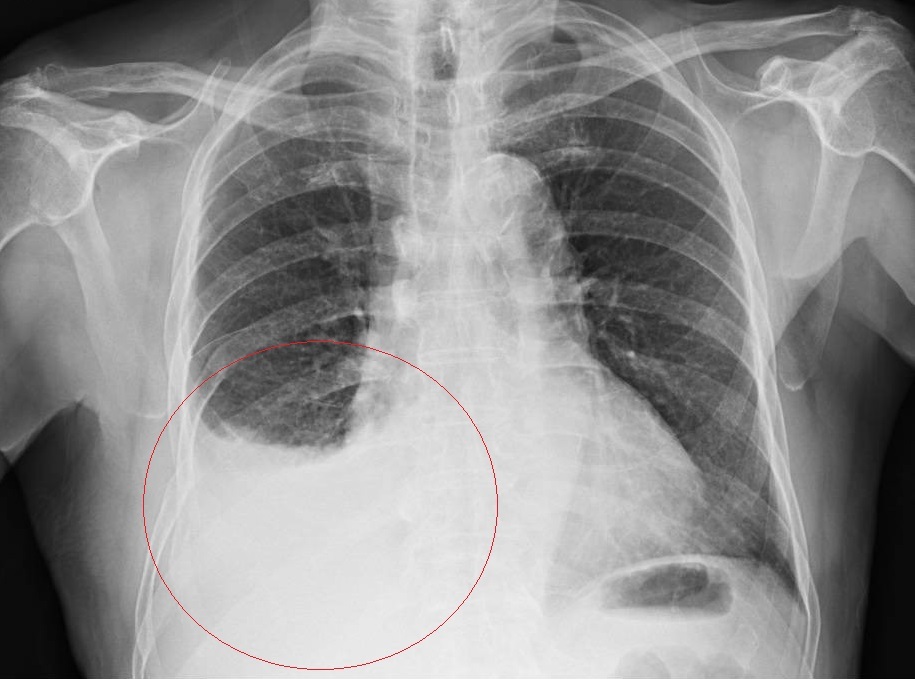

▲ X光片顯示老翁嚴重血胸(圖/彰化醫院提供)

林聿騰指出,王老先生到院時臉色慘白,隨時會昏倒的感覺,檢測血液發現其血紅素低至5g/dl,比一般男性正常的14~18低了很多,有休克之虞,而且胸膜腔內滿是血液,研判胸腔內一定有出血點,經內視鏡手術止住血管的出血點並輸血後才開始好轉。